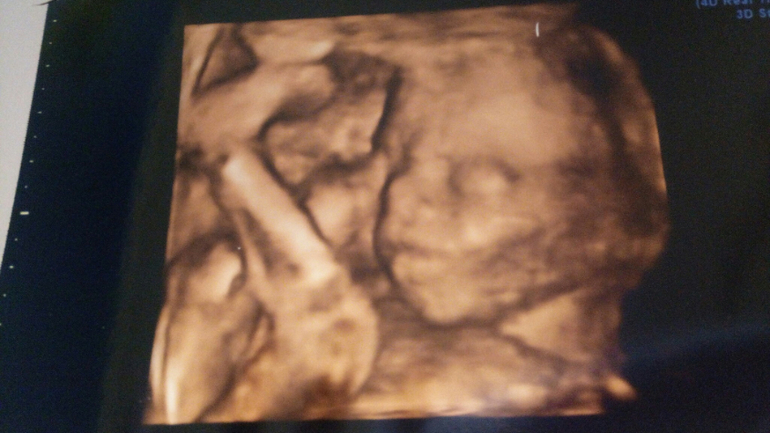

Результаты: УЗИ, КТГ, доплера, скринингаСегодня видели нашу красавицу

Все вроде в порядке, но смущает размер головы, по нижней границе (((